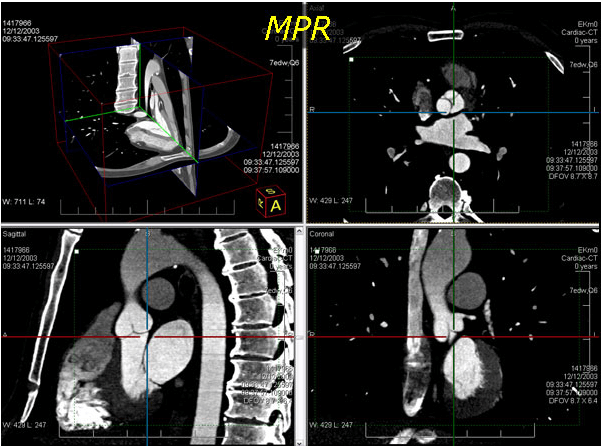

leadtools 为医学影像开发人员提供了一整套2d切片和3d重建技术,如mri和ct栈,而且提供了5种不同的3d重建技术:mpr、vrt、mip、minip和ssd。全面支持裁剪、缩放、变焦、视角控制、透明度、灰度、投影、测量、标注。您可以很容易的从任意的2d切片图像构建3d模型。而这一切在web端仍然可用。只需要简单的几行代码,拖拽一个控件就可以实现非常强大的3d重建功能。